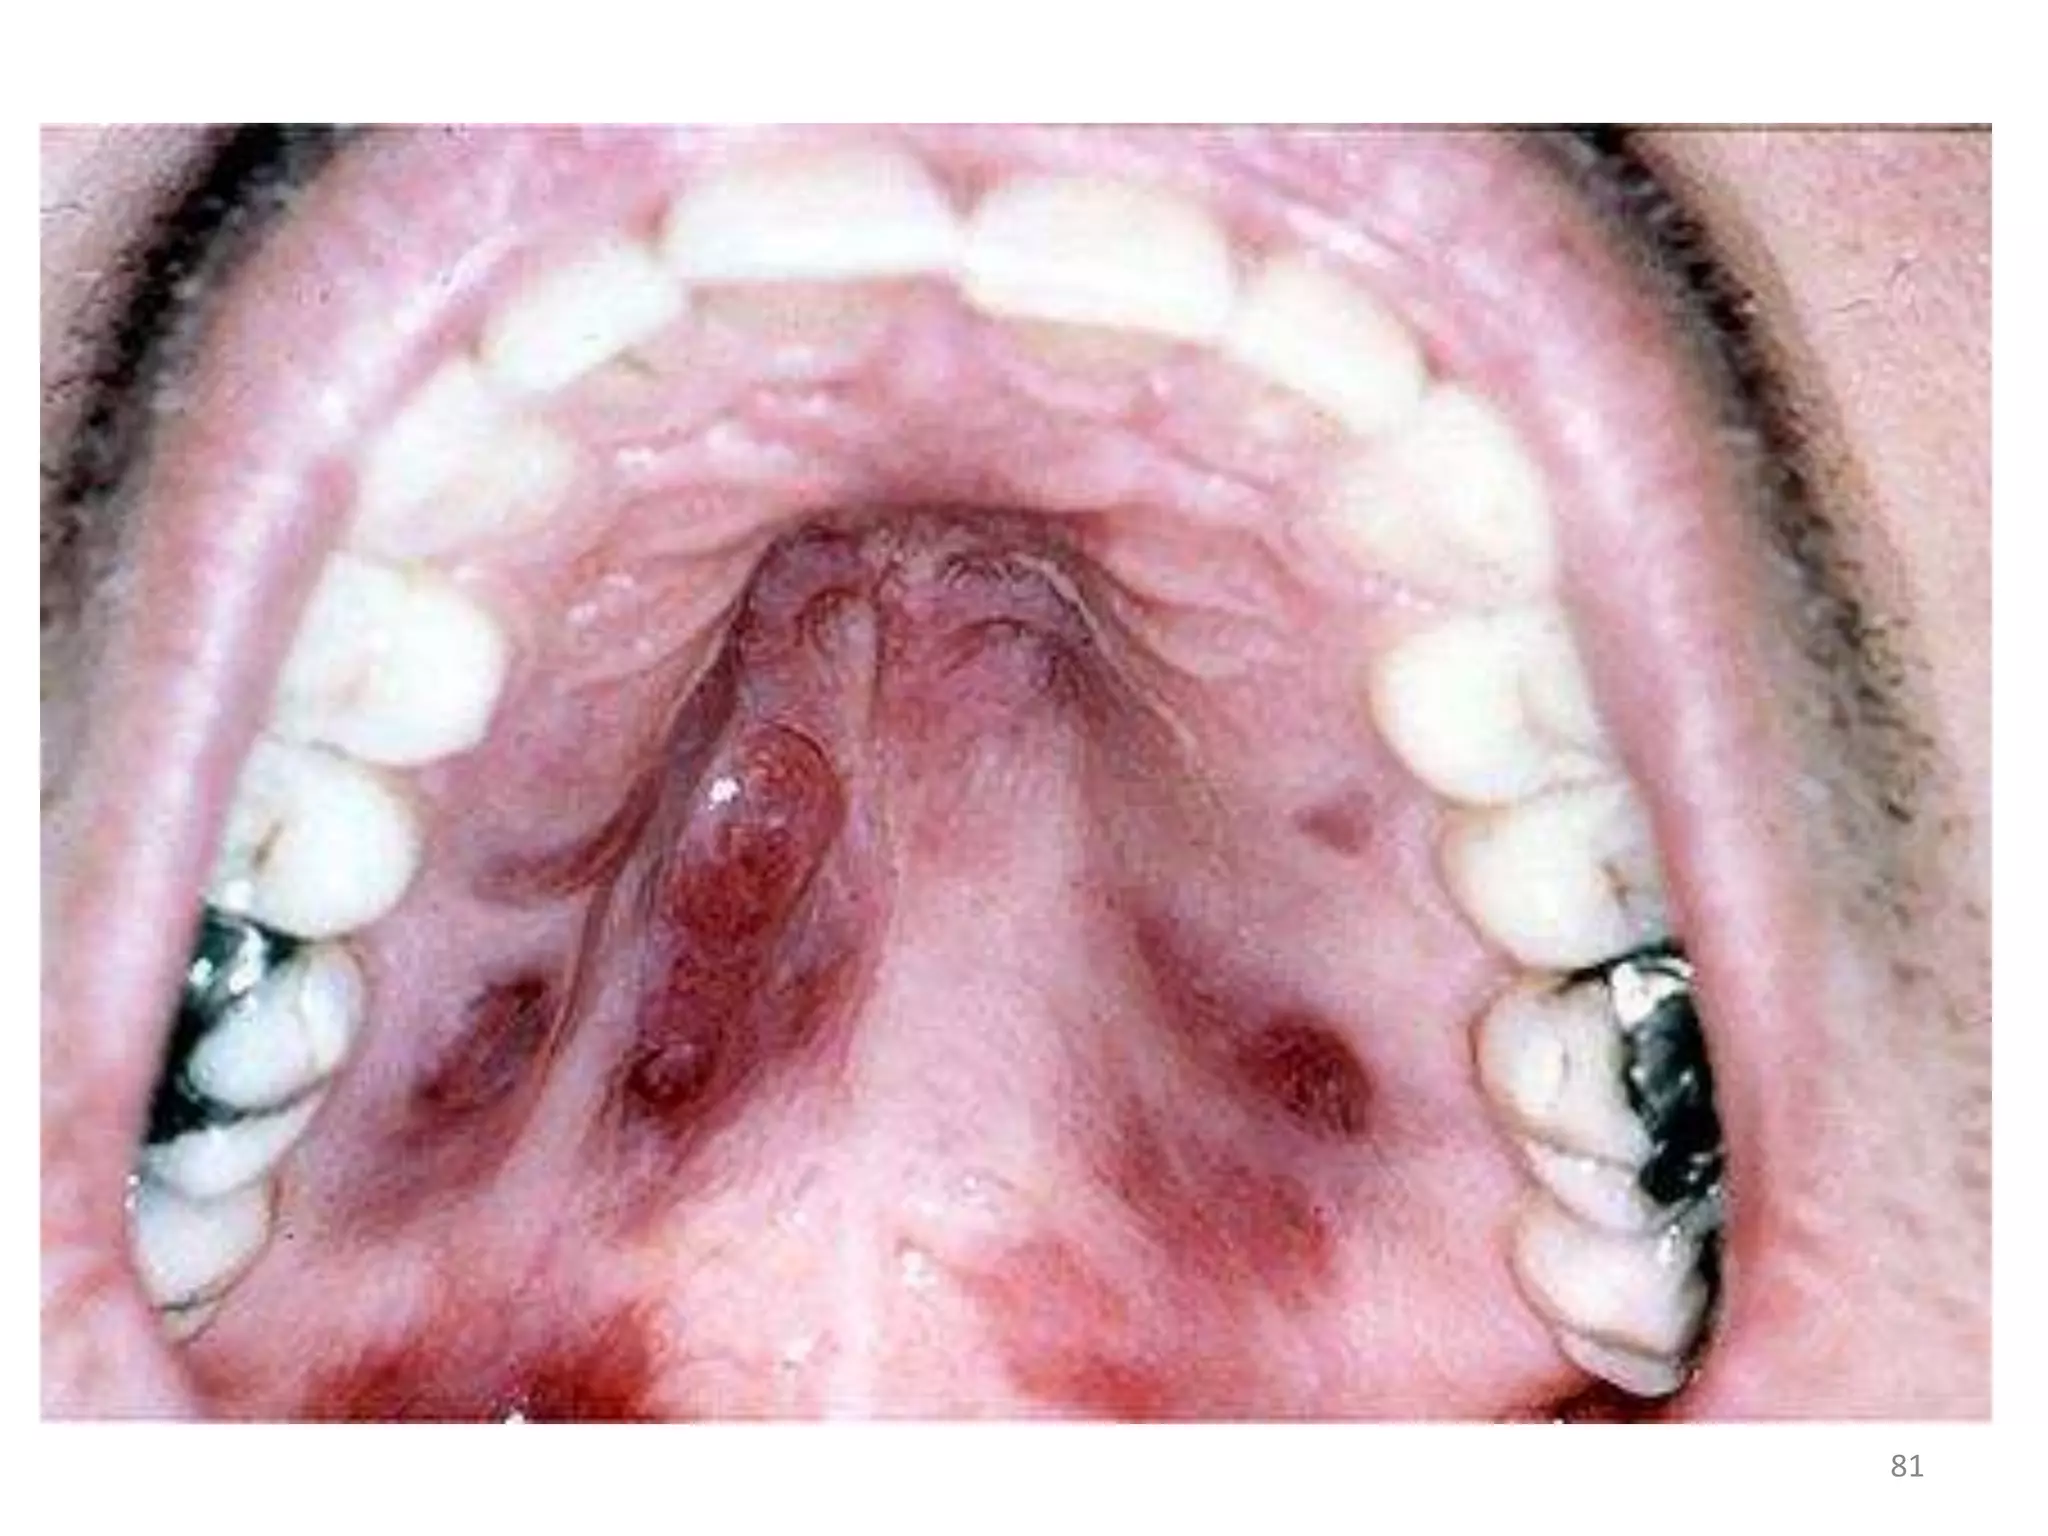

KAPOSI SARCOMA

• Appearance: Oral lesions appear as reddish

purple, raised or flat

• Size ranges from small to extensive.

• Oral and GI tract lesion present as purple

raised lesions at palate, gums, oesophagus,

stomach and large bowel.

Hepatospleenomegaly may be present.

• Definitive diagnosis: biopsy and histological

examination.

• No curative therapy-antiretroviral therapy,

radiation treatment, chemotherapy and

sclerosing agents have been, used to control

oral lesions .

KAPOSI SARCOMA •Appearance: Oral lesions appear as reddish purple, raised or flat • Size ranges from small to extensive. • Behavior is unpredictable. • Cutaneous lesions present as purple non pruritic papules eapicially on the nose,legs and genitals and crease line distribution over the trunk.satellite lesion, brusing,local lymphadenopathy and edema are typical. 78

• 79.

• Oral andGI tract lesion present as purple raised lesions at palate, gums, oesophagus, stomach and large bowel. Hepatospleenomegaly may be present. • Pulmonary lesions present as breathlessness, cough,hemoptysis, chest pain and fever. 79

• Definitive diagnosis:biopsy and histological examination. • No curative therapy-antiretroviral therapy, radiation treatment, chemotherapy and sclerosing agents have been, used to control oral lesions . 82